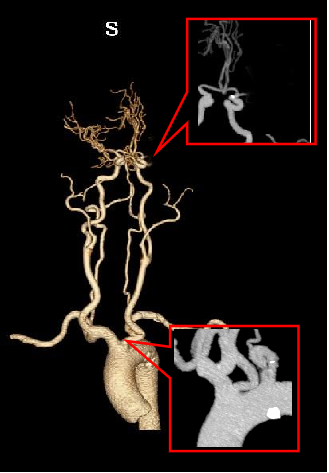

单弯导管辅助长泥鳅导丝置于LC1末端,交换Infinity长鞘至LC1,DSA:LM闭塞。